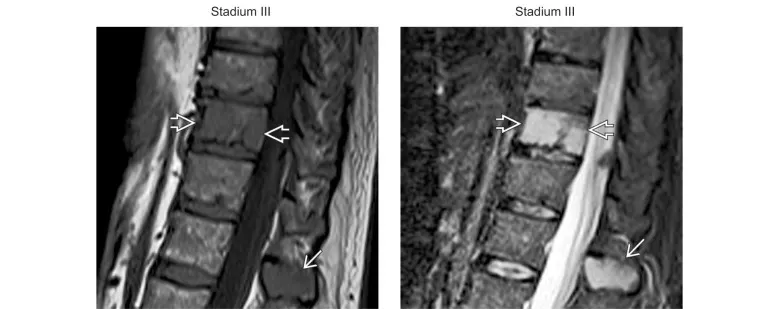

(Gauche) L’IRM T1 sagittale à travers la colonne thoracolombaire montre le remplacement de la graisse normale de la moelle asseuse par des foyers de faible signal T1 de l’infiltration d’un myélome impliquant le corps vertébral (⇨) et la moelle du processus épineux (→). (Droite) L’IRM STIR sagittale chez le même patient montre une augmentation du signal STIR impliquant le corps vertébral (⇨) et la moelle du processus épineux (→). Bien que des études aient suggéré d’épargner les éléments postérieurs dans le myélome multiple, l’imagerie avancée réfute cette affirmation.